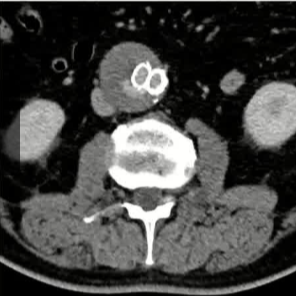

栓塞材料的可及性(例如病灶栓塞材料的可到达性)accessability (e.g. reachability of the nidus) 栓塞的预期深度intended deepness of embolization 如果需要让栓塞填满最后1mm 预期效果(例如:门静脉栓塞的炎症)intended effect (e.g. inflammation in PVE) 凝血状态(达到止血效果所需的时间)coagulation state (duration until hemostasis) 并发症(过敏、心律不齐、肺动脉高压、肝纤维化等)comorbidities (allergies, arrythmia, pulmonary hypertension, lung fibrosis etc.) 处于危险中的结构(包括下游部分-downstream和反流部分) structures at risk (downstream & backwash) 靶病变定位(浅层与深层) target lesion localization (superficial vs. deep) 不会选择一些会引起炎症的东西,因为那会病人来说真的很痛苦浅层病变 栓塞所需的速度(例如:危及生命的出血情况)required speed of embolization (e.g. life threatening hemorraghe) 院外专业人员(DSA技术人员和介入放射科医生)local expertise (technicians & IR's) 可用性与定价 availabilty & pricing Patient assessment for the choice of the ideal liquid emboli 影像学 62岁 男性